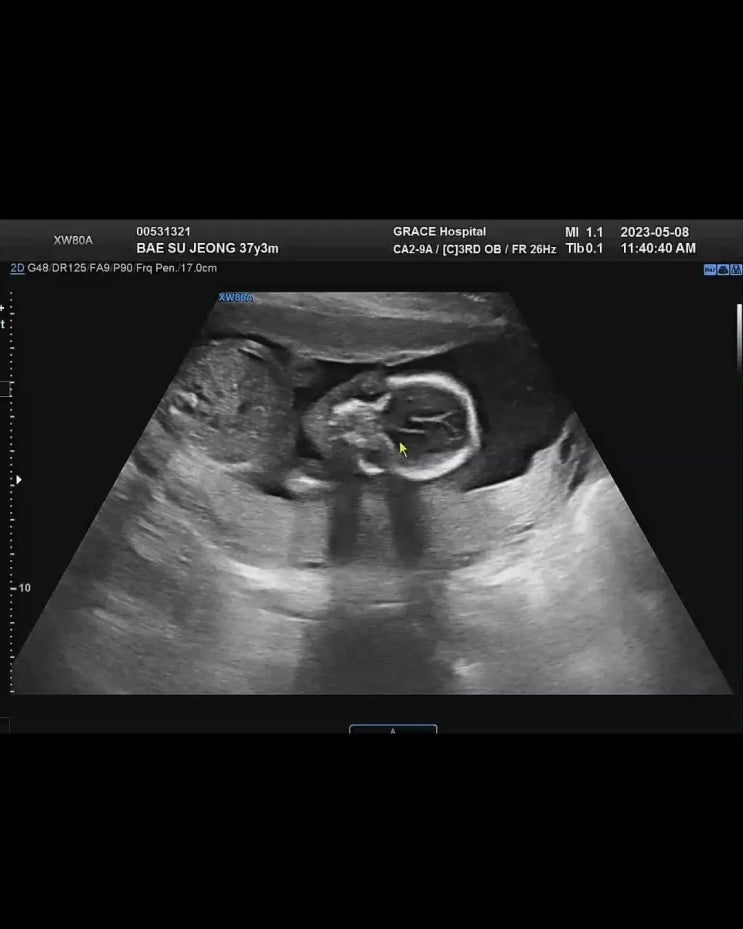

[임신 18주~21주] 임산부장염, 임산부코로나, 정밀초음파, 임당소변검사

나는 진짜 생전 잔병치레가 없는 편인데 이상하게 축복이를 임신하고 온갖 중병테러를 당하고있다. 없던 비...

[임신14주~17주] 보건소철분제, 임산부요가, 체중관리

임신소양증 임신 15주쯤 지나니 피부가 가려운 증세는 많이 완화되었다. 16주 덕양구보건소 철분제신청 16...